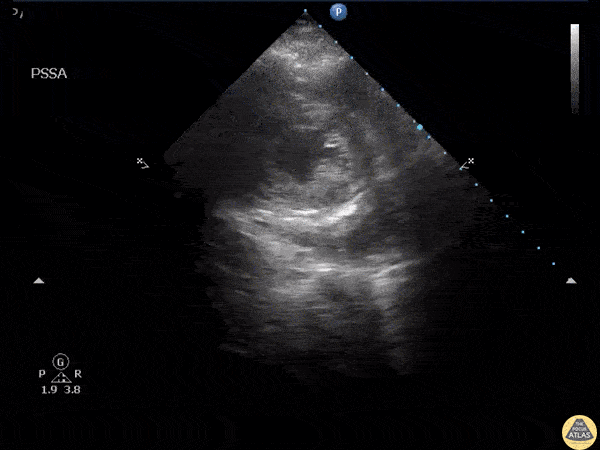

Parasternal short axis view of a Post-CABG intrapericardial hematoma. Image courtesy of Robert Jones DO, FACEP @RJonesSonoEM Director, Emergency Ultrasound; MetroHealth Medical Center; Professor, Case Western Reserve Medical School, Cleveland, OH View his original post here